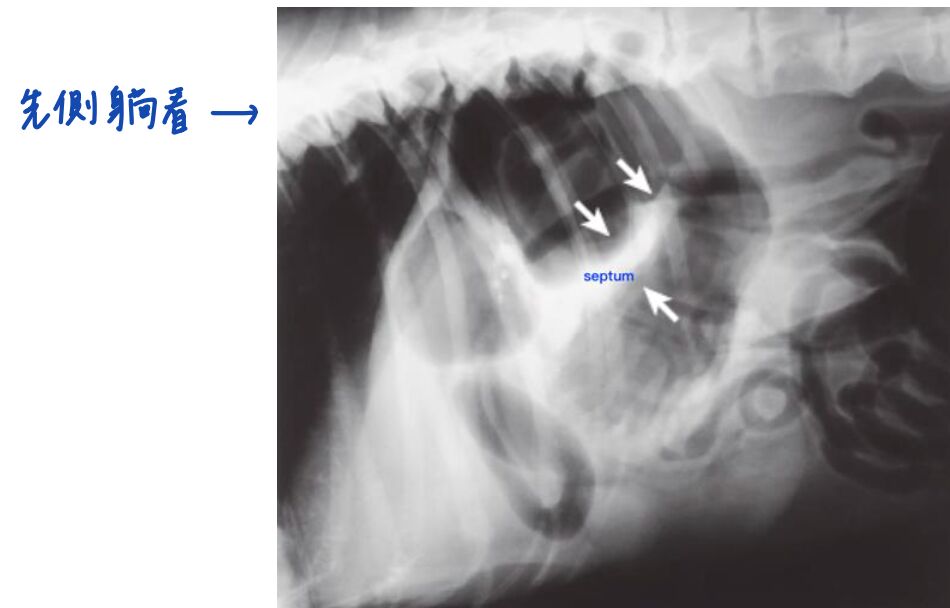

• X-ray 是診斷 GDV 的重要工具

• 側躺看到double bubble / reverse C / popeye sign(三個名字都是指下圖的影像),中間有 septum (代表有扭轉)

• 如果同時有穿孔,就可能看到氣腹 pneumoperitoneum

683a97d5af4fc.jpg

• 如果在 lateral view 已經看到上述影像,就不要再拍 VD 了!

• 因為每一次翻身或仰躺都可能會影響血管,而導致休克